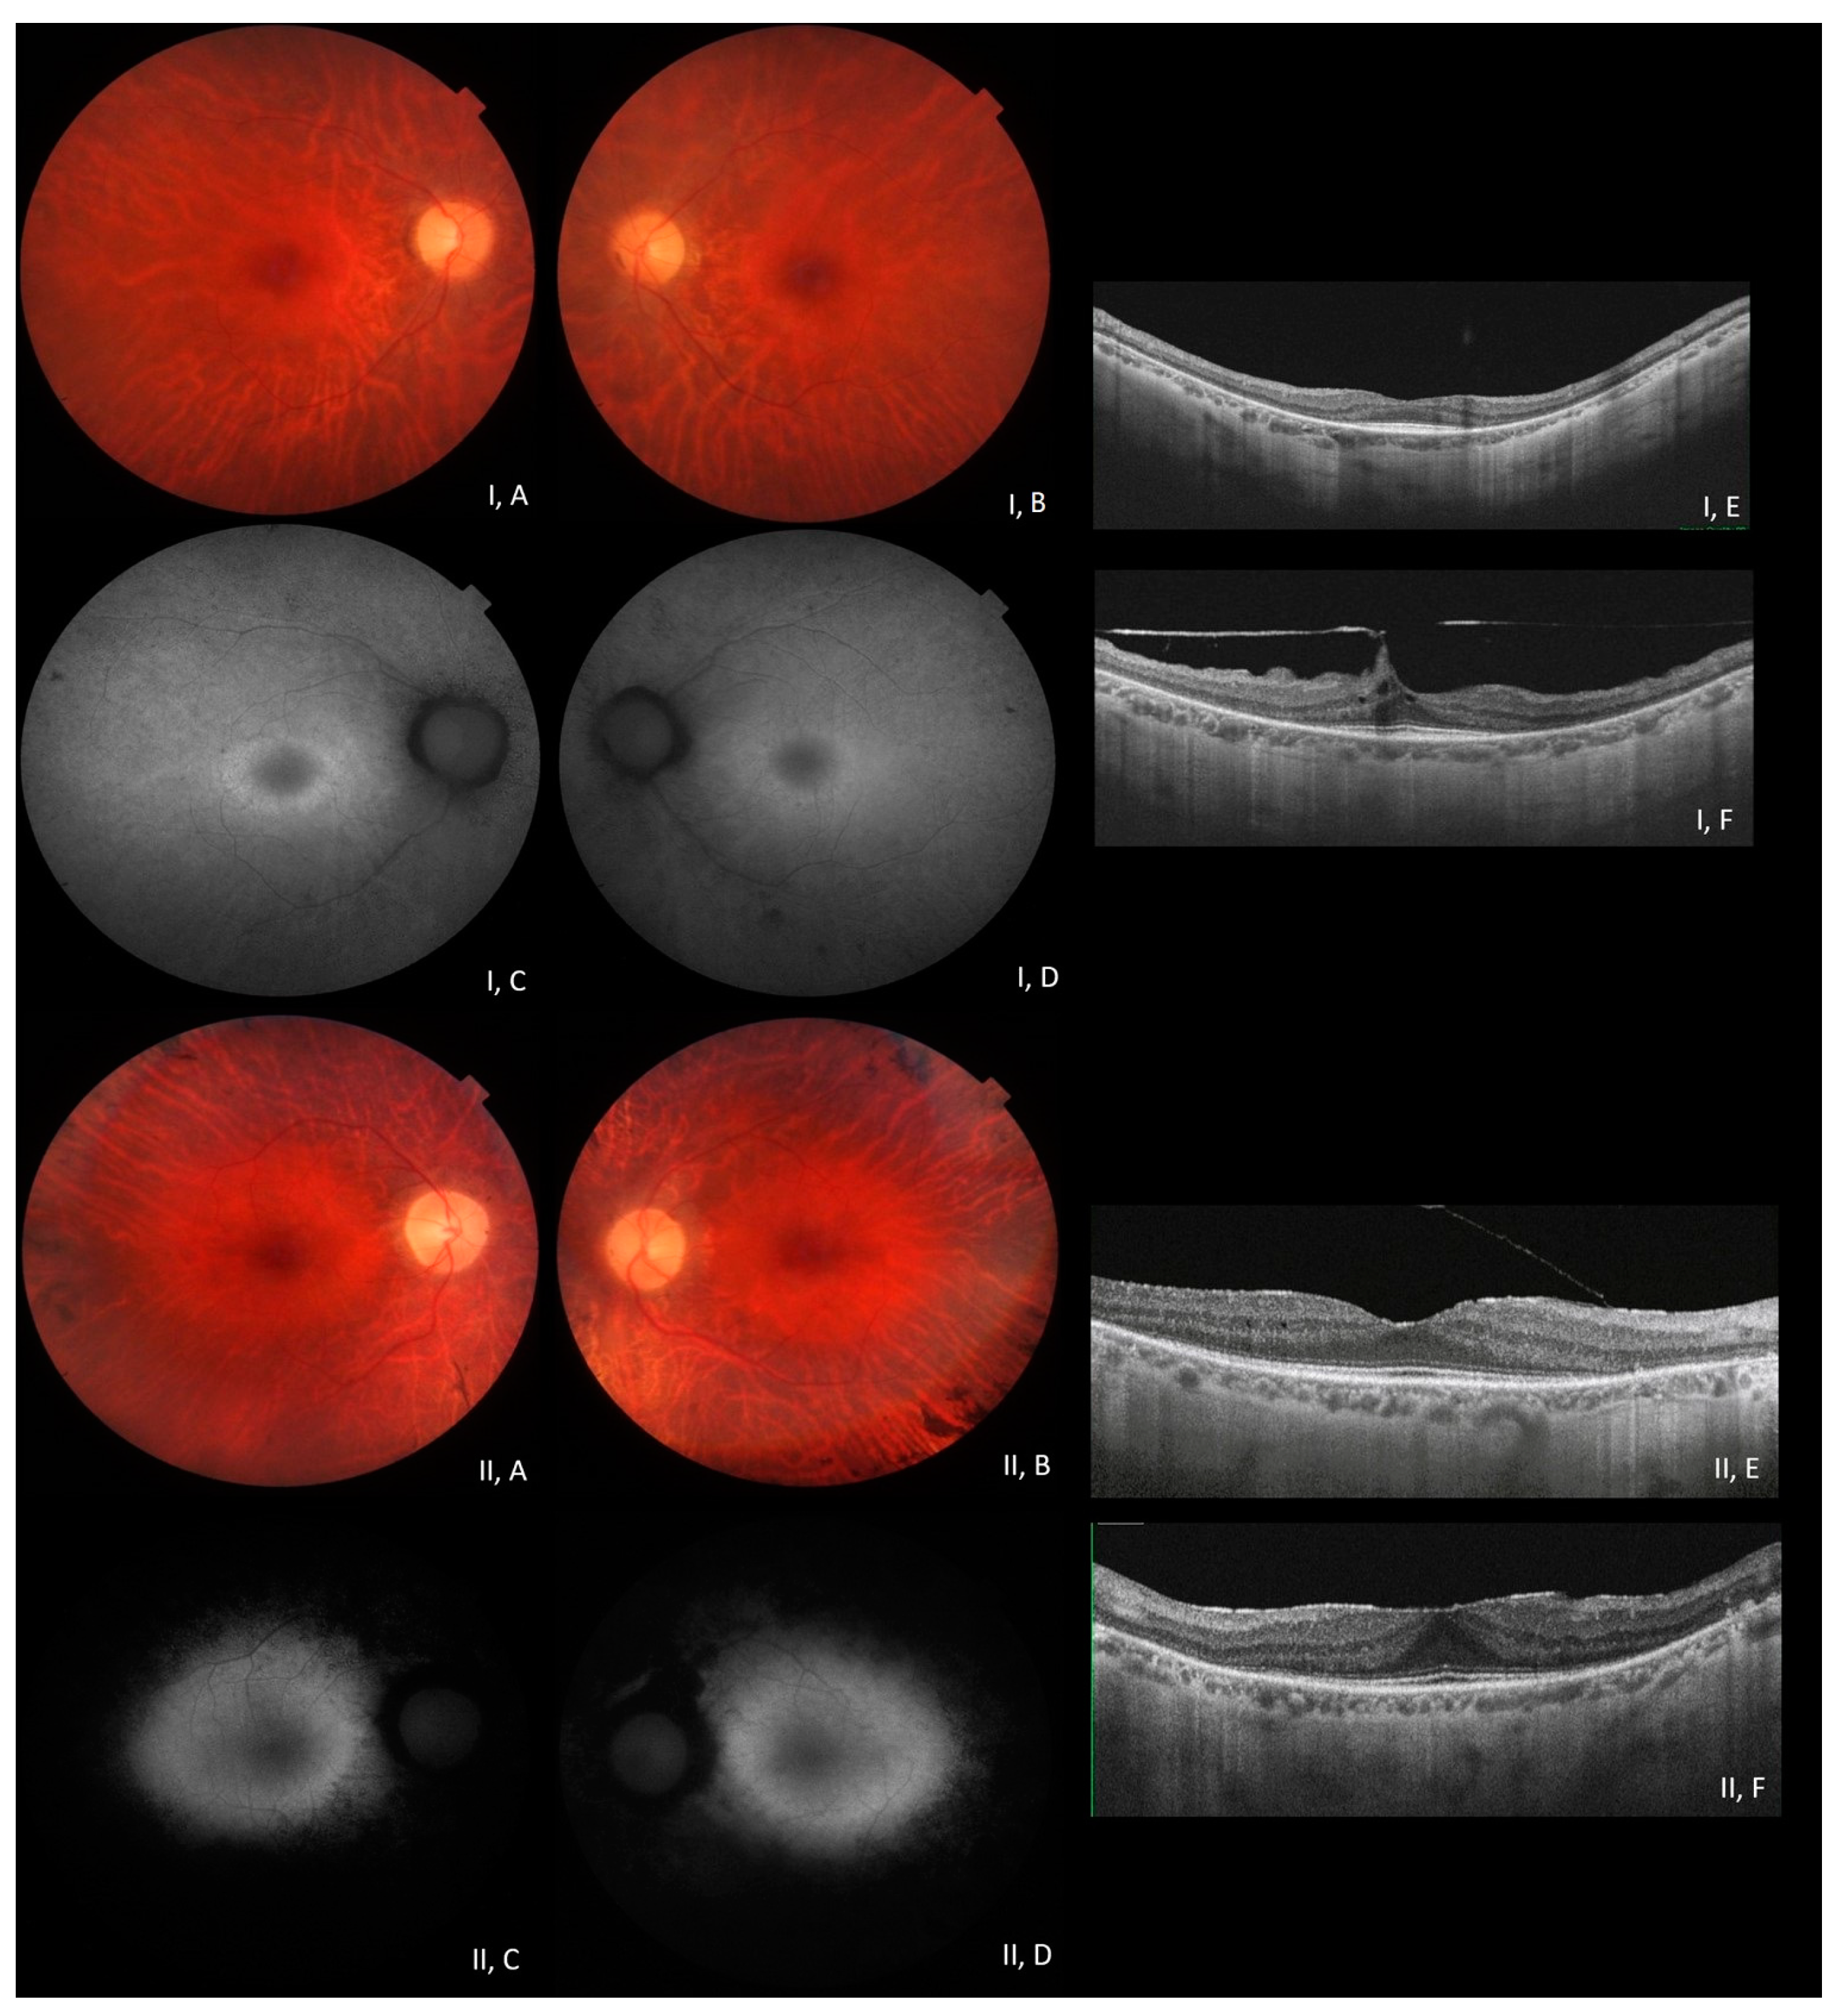

3.2. Phenotype–Genotype Correlation in RP1-Associated ADRP